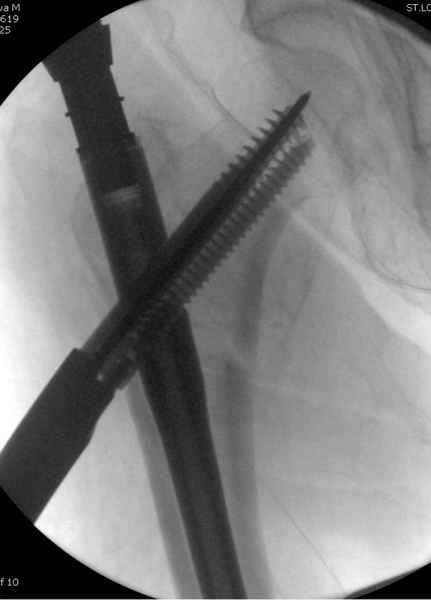

В общем, сделали. См. приложение.

Длина и из-за этого ось получились не совсем такие, как хотелось бы, все-таки срок после той операции уже 6 недель. Может быть, стоило провести дистракцию аппаратом неделю-другую. Заранее спасибо за комментарии и критику.

Наверное так и надо сделать. Будет непросто предотвратить при введении смещение Гаммы кнаружи через имеющийся дефект кортикала. Уверен, Александр Николоевич, Вы с эти справитесь. Удачи!